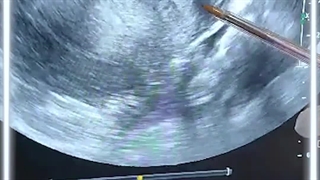

سونوگرافى ترانس واژینال در مرکز سروش

دکترمحمدزاده متخصص سونوگرافی

متخصص رادیولوژی وماموگرافی وغربالگری جنین با ۲۰ سال سابقه